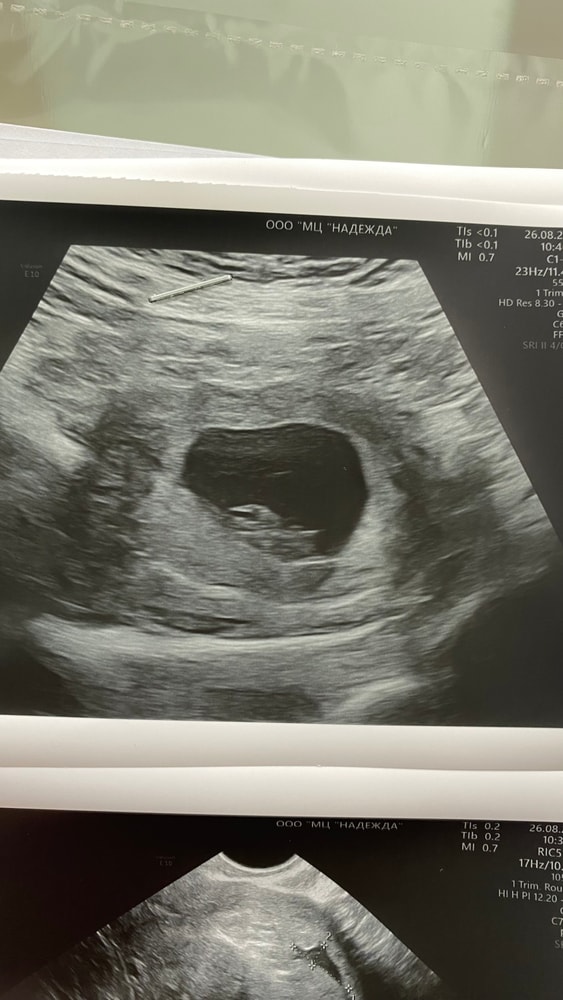

девочкиии привет милые🌸👋🏻 спешу с вами поделиться о том, что тот замер желточного мешочка 7,0 мм был ошибочным слава Богу!!🙏🏻😭😭 то то я точно помню, что узистка про него ничего не говорила, а просто значит этот размер был размером другого человека, который был до меня🤷♀️ сегодня сходила на узи и наш мешочек 4,9 мм на 10,2 недели🙌🏻🙌🏻 я

как раз закончилась тревога по отслойке и на тебе теперь этот мешочек🫠🫠🤌🏻🤌🏻🥹 нет чтобы жить спокойно нам🥲😂 а если серьезно, то врач узи сказала да, он чуть больше, но это норма и все показатели у вас в срок🤷♀️ в 9 недель он был 4,7 мм, но там смотрела другой узист. кто-нибудь сталкивался с таким размером ЖМ?🥹 поделитесь, пожалуйста 🙏🏻